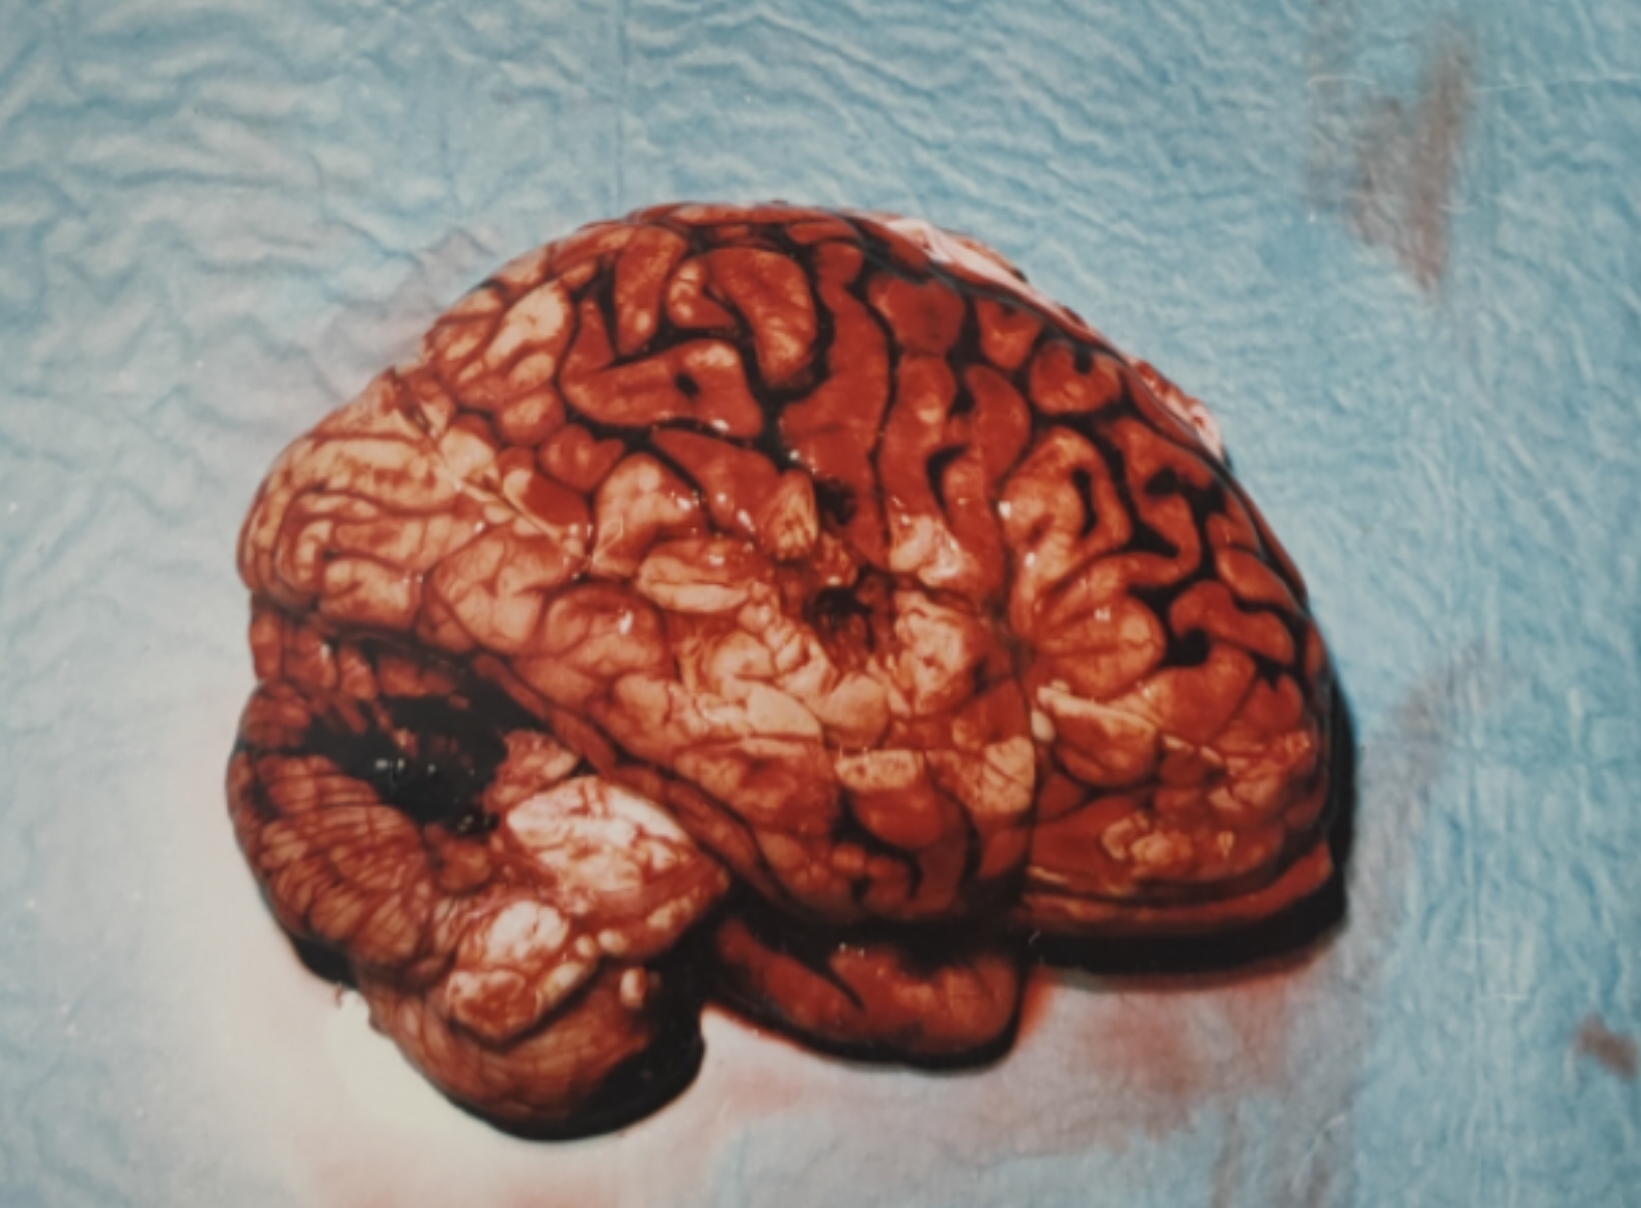

今天来讲讲上面那个脑子的事

那些黑色的部分都是脑外伤引起的蛛网膜下腔出血,程度不算重,顶多是个轻伤二级( ゚∀。)

要命的是第一张图正中间的部分那两个圆形的小黑点,第二张图对应的位置可以看到脑组织的星芒状绽裂

尸检倒是简单,脑子都成那样了还有啥可说的( ゚∀。)

解剖意见:枪击致重度颅脑损伤死亡